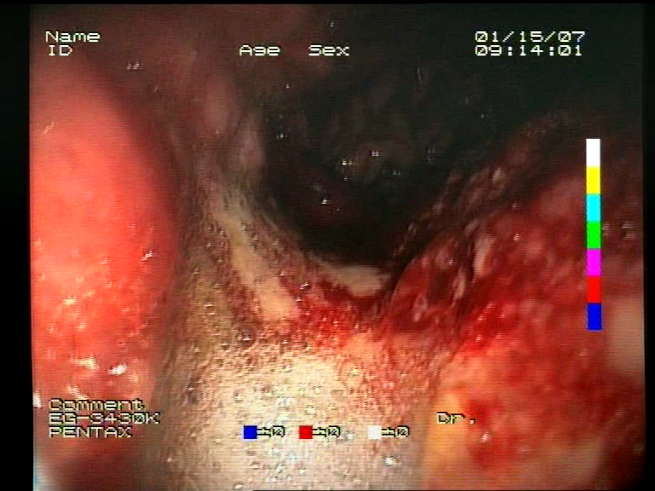

As a result of the design process, nine high-level features (denoted F1–F9) were defined. The features are proposed with simple definitions that also include exemplary images, presented in Table 1. For each image, a blue annotation is presented, illustrating the image regions where the feature is hypothetically present.

Table 1.

Definitions of the nine proposed visual features of endoscopic bleeding. For each image, a blue annotation is presented, which illustrates the area of the image where the feature is hypothetically present.